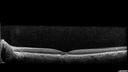

Macular Telangiectasia (MacTel) and Pattern Dystrophy424 views71 year old man with diabetes for 5 years and blurred vision in the left eye. VA 20/25 OD, 20/50 OS. OCT OS shows MacTel     (0 votes)

70 year old man The vision in the left eye is cloudy. The right eye is OK.  Diabetic for 5 years not on insulin.

VA OD: Dcc20/25-2 NccJ3

VA OS: Dcc20/50-1 PHNI NccJ16

IOP: TP: OD:17 OS:18

Images show MacTel OS and pattern dystrophy OU